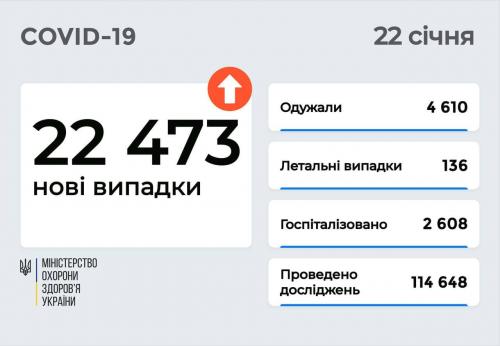

Пів тисячі - у важкому стані, 9 жителів Рівненщини померли за добу від коронавірусу